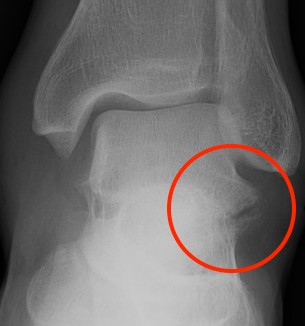

X-ray

Best seen on mortise view

McCrory-Bladin Classification

| Type I |

Type 2A |

Type 2B | Type 3 |

Chip fracture Doesn't involve articular surface |

Larger fracture Involves articular surface talofibular & subtalar join Undisplaced |

Larger fracture Involves articular surface talofibular & subtalar joint Displaced |

Comminuted fracture Involves articular surface talofibular & subtalar |